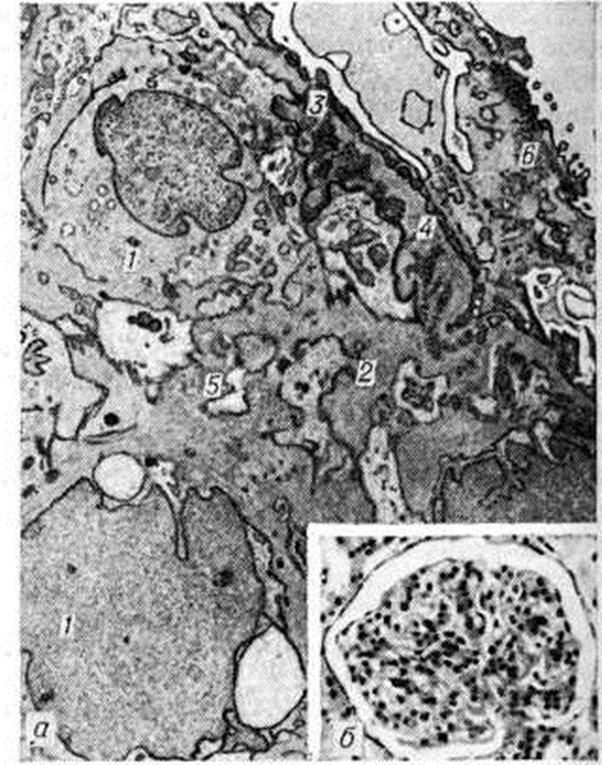

Реже ему предшествуют другие причины: пневмонии, пищевые токсикоинфекции, охлаждение, введение вакцины, сывороток, медикаментов и так далее. Реже ему предшествуют другие причины: пневмонии, пищевые токсикоинфекции, охлаждение, введение вакцины, сывороток, медикаментов и так далее. Типирование стрептококков, выделенных из зева больных Гломерулонефрит, показало, что в 78% случаев обнаруживается тип 12β-гемолитического стрептококка группы А. Преобладание 12 типа стрептококка отмечается как в спорадических случаях, так и при вспышках заболевания. В жарких странах развитию Гломерулонефрит особенно часто [в 85% случаев, по данным Диллона (Н. С. Dillon), 1967] предшествуют кожные болезни (пиодермия, импетиго, рожа); у таких больных, как правило, высеиваются пиогенные стрептококки. В сыворотке крови больных Гломерулонефрит наиболее часто обнаруживаются антитела к типу 12 стрептококка. Почти у 51% больных острым Гломерулонефрит стрептококковые антигены обнаруживаются в крови и выявляются в клубочках при иммунофлюоресцентной микроскопии [Сигал (В. С. Seegal), 1965; Андрес (G. A. Andres) с соавторами, 1966]. Часто обнаруживаются также антистрептолизин-О, антигиалуронидаза и антистрептокиназа. Однако постстрептококковый острый Гломерулонефрит с 50-х годы стал встречаться реже, что связано в значительной степени с применением мощных антибактериальных препаратов. Теснее связан со стрептококковой инфекцией Гломерулонефрит при подостром септическом эндокардите, что может проявляться не только классическим очаговым эмболическим нефритом [Лелейн (М. Н. F. Lohlein), 1910], но и диффузным поражением почек. Частота поражения почек при подостром септическом эндокардите может быть высокой — до 50%, при ревматизме (по секционным данным) — до 10,5%. Описан Гломерулонефрит и при стафилококковом эндокардите. Пневмонии осложняются Гломерулонефрит в 1—3% случаев. Роль брюшного и сыпного тифа, малярии в развитии Гломерулонефрит невелика. При малярийном нефрите находят отложение малярийного антигена в клубочках в составе иммунного комплекса наряду с иммуноглобулинами, комплементом, фибрином. При туберкулёзе клинический, картина Гломерулонефрит может оказаться ведущей. По данным В. В. Сура, А. М. Вихерта (1966), мембранозный Гломерулонефрит легко воспроизводится у животных при введении микобактериального адъюванта, то есть стимулятора процессов иммуногенеза (смотри полный свод знаний Адъюванты). Гломерулонефрит при туберкулёзе у человека описан Б. М. Коваливом и В. Ф. Подуговским (1957). Гломерулонефрит при сифилисе, протекающий обычно по нефротическому типу, редок. К инфекционно-иммунной группе Гломерулонефрит относят также малоизученные вирусные Гломерулонефрит при кори, ветряной оспе, вирусном гепатите, энтеровирусной инфекции. В группу Гломерулонефрит неинфекционно-иммунного происхождения входит Гломерулонефрит, развивающийся после ряда антигенных воздействий (сывороткой, вакциной, пыльцой растений, ядом насекомых, лекарственными и другими хим. веществами, пищевыми продуктами при индивидуальной непереносимости), а также Гломерулонефрит, возникающий при нарушении венозного оттока (частичный тромбоз почечных вен, нижней полой вены, сдавливающий перикардит, недостаточность трёхстворчатого клапана). Охлаждение, особенно при высокой влажности, может способствовать возникновению Гломерулонефрит или его обострению. ПатогенезОбщепринятой патогенетической классификации Гломерулонефрит пока нет. Наиболее обоснованной является иммуноаллергическая концепция, подтверждаемая клинический, иммунологический, экспериментальными и иммуногистохимический данными. Гломерулонефрит возникает обычно после инфекции или другого воздействия (вакцинация и так далее) при различной длительности латентного периода, хотя известно и его интраинфекционное развитие [Раммелькамп (С. Н. Rammelkamp), 1963]. В сыворотке крови больных Гломерулонефрит достаточно часто обнаруживают противопочечные антитела. Однако титры их не всегда коррелируют с клинический, проявлениями острого Гломерулонефрит, что позволяет ряду авторов рассматривать эти антитела как спутники процесса, не имеющие патогенетического значения. Титр комплемента при Гломерулонефрит почти постоянно снижен, что свидетельствует о потреблении комплемента в ходе иммунологический реакций. Гломерулонефрит легко воспроизводится в эксперименте с помощью гетерологических антипочечных сывороток, получаемых при иммунизации животных почечным антигеном животного другого вида [В. К. Линдеман, Масуги (М. Masugi)]. Как показали опыты с меченой противопочечной сывороткой, связывание ее на базальной мембране клубочков происходит в течение нескольких минут [Прессман (D. Pressman), 1948], возникновение клинко-морфологически проявлений Гломерулонефрит связано с фиксацией комплемента в клубочках и зависит от комплементсвязывающей способности вводимой противопочечной сыворотки. Для воспроизведения экспериментального Гломерулонефрит по Масуги используется противопочечная сыворотка птиц, не обладающая способностью связывать комплемент млекопитающих. Между введением сыворотки и возникновением Гломерулонефрит проходит латентный период (6—8 дней), необходимый для образования комплементсвязывающих противопочечных аутоантител. В патогенезе этого варианта экспериментального Гломерулонефрит можно выделить две иммунологический фазы — фиксацию экзогенных антител в почках и последующее образование аутоантител, способных связывать комплемент. Эксперименты с использованием адъювантов типа Фрейнда [Хейманн (W. Heymann), 1959] демонстрируют значение общей иммунологический реактивности для возникновения Гломерулонефрит. Если введение животным гомологичного почечного антигена не вызывает у них развития Гломерулонефрит, то введение его в составе микобактериального стимулятора позволяет воспроизвести Гломерулонефрит Иммуноаллергическая гипотеза патогенеза Гломерулонефрит подтверждается и данными, полученными при изучении роли стрептококков в его возникновении. Как показали опыты Кавелти (P. A. Cavelti, F. S. Cavelti, 1945), Гломерулонефрит удаётся вызвать введением животным смеси из ткани почки и стрептококков. Возможно, стрептококк меняет свойства белков ткани почки, делая их антигенными; не исключено и его адъювантное действие. Антиген стрептококка (М-протеин) по своей химических природе относится к гликопротеинам. Доказано антигенное сродство базальной мембраны капилляров клубочков и оболочек стрептококков нефрогенных штаммов. Часть М-протеина фиксируется в клубочках, часть циркулирует в кровяном русле, вызывая образование антител. Комплексы, образующиеся в результате реакции антиген—антитело, задерживаются клубочковым фильтром с фиксацией комплемента. Образование иммунных комплексов с фиксацией комплемента может происходить и непосредственно в клубочках. Иммунные комплексы повреждают почку. При иммуноморфологические изучении иммунокомплексного Гломерулонефрит скопления комплекса обнаруживаются субэндотелиально или субэпителиально в виде глыбок. Реже находят линейное расположение отложений (депозитов) иммунных комплексов, что свойственно для некоторых форм пролиферативного Гломерулонефрит, нефрита трансплантированной почки. В дальнейшем независимо от расположения депозитов в результате отчасти хемотаксического действия С3-комплемент системы (смотри полный свод знаний Комплемент) сегментоядерные лейкоциты фиксируются на капиллярных петлях, слущивают или отодвигают эндотелий, тесно контактируют с базальной мембраной. Лизосомальные ферменты лейкоцитов воздействуют на базальную мембрану и вызывают её повреждение. Участие клеточных механизмов иммунитета в патогенезе Гломерулонефрит, более характерных для мембранозного Гломерулонефрит, подтверждается возможностью переноса экспериментального адъювантного нефрита лимфоцитами (но не сывороткой) больного животного [Хесс (Е. V. Hess) с соавторами, 1962] здоровому реципиенту. Механизм такого переноса объясняется цитопатическим действием лимфоцитов в эксперименте [Холм (G. Holm), 1966], в том числе в культуре почечной ткани (Т. Г. Троянова с соавторами, 1973, 1974). Наряду с иммунными механизмами имеет значение сочетающееся с ними изменение процессов коагуляции; применение антикоагулянтов предупреждает при Масуги-нефрите тяжёлое поражение клубочков. Патологическая анатомияМорфологически изменения почек при Гломерулонефрит отличаются большим разнообразием и наблюдаются во всех их структурных элементах, но ведущим является диффузный гломерулит, в основе которого лежит воспаление обычно иммунной природы. Изменения клубочков при Гломерулонефрит были подробно изучены после внедрения в клинический, практику пункционной биопсии почки с использованием методов гистохимии (смотри полный свод знаний Гистохимические методы исследования), электронной микроскопии (смотри полный свод знаний), иммуногистохимии (смотри полный свод знаний Иммуноморфология), авторадиографии (смотри полный свод знаний) и другие. На основании изучения почечного пунктата [В. В. Серов, Нольтениус (Н. Noltenius), Диттрих (P. Dittrich), Бруэр (D. В. Brewer)] при Гломерулонефрит различают следующие изменения клубочков: минимальные, мембранозные, пролиферативные (интра и экстракапиллярные), экссудативные (интра и экстракапиллярные), мембранознопролиферативные, фибропластические. В этой классификации гломерулярных изменений, которая является дальнейшим развитием схем Эллиса (A. Ellis) и Белла (Е. Т. Bell), пролиферативные, мембранозные и фибропластические изменения — основные. Минимальные изменения (при световой микроскопии) сводятся к незначительному очаговому утолщению базальных мембран капилляров клубочков и гиперплазии клеток эндотелия лишь в отдельных петлях. Электронная микроскопия обнаруживает начальные изменения в виде редукции малых отростков подоцитов без выраженных изменений базальной мембраны капилляров клубочков [foot process type, по Чергу (J. Churg)]. Иммуногистохимический исследование даёт отрицательные результаты. О природе этих изменений единого мнения нет. Одни исследователи рассматривают их как проявление Гломерулонефрит, другие — как самостоятельное заболевание (липоидный нефроз детей). Мембранозный Гломерулонефрит (II тип по Эллису) описан впервые Беллом. Он предложил относить к мембранозному Гломерулонефрит клинический, случаи липоидного нефроза (идиопатический нефротический синдром), при к-рых гистологически обнаруживается утолщение (рисунок 1 в) и расщепление базальных мембран капилляров клубочков с наличием «шипиков», выявляемых методом серебрения, при отсутствии пролиферации клеток клубочка. В дальнейшем мембранозные изменения были обнаружены при гистологический исследовании почек (биопсия) не только при идиопатическом нефротическом синдроме, но и при других клинический, формах Гломерулонефрит. Исходным моментом в повреждении базальной мембраны капилляров клубочков считают фиксацию на ней аутологичных иммунных комплексов (рисунок 1 а), что доказывается методами иммуногистохимии (на базальных мембранах выявляются иммуноглобулины и комплемент) и электронной микроскопии (выявление депозитов на эпителиальной стороне мембраны). При мембранозном Гломерулонефрит, обозначаемом как диффузная мембранозная гломерулопатия (перимембранозный, или экстрамембранозный, Гломерулонефрит, липоидный нефроз взрослых), на наружной стороне базальной мембраны появляются гранулярные депозиты (рисунок 1 б) иммунных комплексов и отложения плазменных белков, тогда как внутренняя сторона мембраны имеет обычные контуры. Депозиты отделены друг от друга выступами lamina densa, направленными в сторону эпителия, в результате чего мембрана имеет вид гребня (мембранозная трансформация по Чергу). В результате «вымывания» депозитов базальная мембрана становится неравномерной плотности. Со временем между депозитами и ножками подоцитов образуются перемычки, они сливаются и уплотняются. Мембрана утолщается за счёт новообразованного слоя кнаружи от депозитов, которые инкорпорируются, подвергаются резорбции и становятся менее осмиофильными. При выраженных мембранозных изменениях пролиферация клеток клубочка отсутствует. Мембранозные изменения считаются морфологически эквивалентом идиопатического нефротического синдрома. Однако протеинурия при мембранозном Гломерулонефрит связана не только с изменениями клубочков, но и с недостаточной резорбцией белка в почечных канальцах. Морфология этой недостаточности представлена дистрофией и атрофией эпителия канальцев, склерозом стромы. Со временем дистрофические изменения почечных канальцев нарастают, выявляется гиалиноз мембран не только клубочков, но и канальцев. При пролиферативном Гломерулонефрит, развитие которого обычно связано с воздействием стрептококка, пролиферация эндотелиоцитов и мезангиоцитов, как правило, сочетается с экссудативными изменениями, инфильтрацией клубочка полиморфно-ядерными лейкоцитами. Отслаивая эндотелий, лейкоциты проникают к базальной мембране капилляров и мигрируют в мезангии (рисунок 2). Их постоянно можно найти рядом с гранулярными субэпителиальными депозитами в виде горбов («humps»), содержащими гетерологичные иммунные комплексы, в состав которых входят стрептококк, иммуноглобулин и комплемент. При электронной микроскопии депозиты иммунных комплексов обнаруживаются в биопсионном материале из почки через 2—4 недель от начала заболевания, но встречаются через 6 недель и более. С лейкотаксическим эффектом комплемента этих комплексов связана инфильтрация клубочка лейкоцитами, развитие иммунного воспаления в его соединительной ткани — мезангии. Повреждения базальной мембраны клубочковых капилляров также обусловлены литическим действием комплемента иммунных комплексов и лизосомальных ферментов лейкоцитов. В результате повреждения базальной мембраны и процессов внутрисосудистой коагуляции в капиллярах клубочков образуются тромбы, а также наблюдается реактивная пролиферация клеток клубочка. Пролиферация эндотелиоцитов сочетается с расширением мезангия, связанным с увеличением количества мезангиоцитов и накоплением мембраноподобного материала — мезангиального матрикса, что характерно для пролиферативного интракапиллярного диффузного Гломерулонефрит (мезангиопролиферативный Гломерулонефрит). Клинической, проявления интракапиллярного Гломерулонефрит различны, однако безусловна определённая зависимость между гематурией и выраженностью пролиферативной гломерулярной реакции. При преобладании пролиферации эпителия капсулы клубочка возникает пролиферативный экстракапиллярный Гломерулонефрит, который рассматривают как морфологически аналог злокачественного «подострого» или прогрессирующего острого Гломерулонефрит [Дженнингс (R. В. Jennings), Эрл (D. P. Earle)]. Этот вид Гломерулонефрит имеет достаточно характерную морфологию в виде так называемый полулуний из пролиферирующих клеток (рисунок 3 а), которые заполняют просвет капсулы и сдавливают капиллярные петли клубочка. Пролиферация клеточных элементов клубочков обычно сочетается с экссудативными экстракапиллярными процессами, появлением среди клеток нитей фибрина. При этом выявляется фагоцитарная функция подоцитов, в цитоплазме которых с помощью электронной микроскопии можно обнаружить множество фаголизосом (рисунок 3 б): перерабатывающих продукты белкового распада. Экстракапиллярная пролиферация возникает как реакция на резкое повреждение капиллярных петель клубочка, которое для экстракапиллярных форм Гломерулонефрит является правилом. Довольно рано клетки «полулуний» претерпевают фибропластическое превращение. В пролиферат врастает соединительная ткань со стороны капсулы, происходит рубцовая облитерация полости капсулы, что ведёт к гибели клубочка. Экссудативный (интра и экстракапиллярный) Гломерулонефрит как самостоятельная форма встречается крайне редко, что, вероятнее всего, связано с ранним лечением Гломерулонефрит стероидными препаратами. Обычно экссудативные изменения в виде скопления экссудата (серозного, фиброзного, геморрагического) в полости капсулы наслаиваются на морфологически проявления другой формы Гломерулонефрит, отражая остроту процесса. В ряде случаев они сочетаются с фибриноидным некрозом капиллярных петель клубочков, что позволяет говорить об экссудативно-некротическом Гломерулонефрит Мембранозно-пролиферативный Гломерулонефрит, хронический латентный или подострый нефрит, гипокомплементарный персистирующий, хронический лобулярный, смешанный, мезангиокапиллярный Гломерулонефрит — одна и та же форма, для которой морфологически характерны пролиферация мезангиоцитов и утолщение стенок капилляров клубочка [Камерон (J. S. Cameron) и соавторами, 1970], а клинически — хронический течение, протеинурия, реже гематурия и в ряде случаев отсутствие эффекта при лечении стероидными гормонами. Хотя за этим типом Гломерулонефрит и утвердился термин «мембранозно-пролиферативный», правильнее называть его мезангиопролиферативным [Мандаленакис (N. N. MandaJenakis) и соавторами, 1971], так как гломерулярные изменения при нем, в том числе и мембранозные, связаны прежде всего с пролиферацией мезангиальных клеток и интерпозицией мезангия. С помощью электронной микроскопии (рисунок 4 а) определяется резкое расширение мезангия за счёт пролиферации его клеток и увеличения матрикса. Расширение мезангия ведёт к его интерпозиции [Аракава и Киммелстил (М. Arakawa, P. Kimmelstiel), 1969] — отростки мезангиоцитов, окружённые мембраноподобным веществом, выходят за пределы соединительной ткани клубочка и, распространяясь вдоль базальной мембраны на периферию капиллярной петли, отодвигают эндотелий. При световой микроскопии выявляется феномен утолщения (рисунок 4,6) и расщепления мембраны. Пролиферация мезангиоцитов, наблюдаемая, как правило, вблизи депозитов иммунных комплексов, может быть ограничена эндотелиальной выстилкой (при этом просвет капилляра сохраняется свободным), либо пролиферирующие клетки прорывают эндотелиальную выстилку и заполняют частично или полностью просвет капилляра. Повышенная секреция пролиферирующими мезангиоцитами тропоколлагена ведёт к накоплению мембраноподобного вещества в стенке и просвете капилляров, что лежит в основе склероза и гиалиноза клубочков. Сужению просвета капилляров способствует также пролиферация эндотелия, однако она значительно уступает пролиферации мезангиальных клеток Изменения подоцитов разнообразны от гиперплазии ультраструктур, отражающей повышенную функциональную нагрузку, до глубокой дистрофии в виде редукции малых отростков, вакуолизации цитоплазмы, ворсинчатой трансформации клеток. Мембранозно-пролиферативный Гломерулонефрит делят на несколько клиническо-морфоиммунологических вариантов (форм): мембранозно-пролиферативный Гломерулонефрит с субэндотелиальными или плотными депозитами, лобулярный Гломерулонефрит, IgA-гломерулопатия (болезнь Берже). Мембранозно-пролиферативный Гломерулонефрит с субэндотелиальными депозитами характеризуется гиперплазией клеток мезангия, расщеплением базальных мембран гломерулярных капилляров (мезангиокапиллярный Гломерулонефрит), субэндотелиальными депозитами (содержащими большое количество иммуноглобулинов, ранние фракции комплемента, пропердин), гипокомплементемией. При мембранозно-пролиферативном Гломерулонефрит с плотными депозитами («болезнь плотных депозитов») гиперплазия мезангия представлена незначительно, и утолщение стенок капилляров обусловлено электронно-плотными депозитами внутри базальной мембраны. В депозитах обнаруживают большое количество С’З фракции комплемента, содержание которой в сыворотке крови снижено; иммуноглобулины в депозитах отсутствуют. О лобулярном Гломерулонефрит, который, как правило, является иммунокомплексным, говорят в тех случаях, когда пролиферация мезангиоцитов происходит в пределах дольки и сопровождается её ранним склерозом и гиалинозом. Основной признак IgA-гломерулопатии, или болезни Берже,— преобладание в субэндотелиальных и мезангиальных депозитах иммунных комплексов IgA и С’З фракции комплемента. Гистологически находят очаговую или диффузную пролиферацию мезангиальных клеток. Фибропластический Гломерулонефрит следует рассматривать как собирательную эволютивную форму пролиферативного, мембранозного и мембранозно-пролиферативного Гломерулонефрит. При всех этих формах Гломерулонефрит в развитии склероза и гиалиноза клубочков основная роль принадлежит мезангиальной трансформации: пролиферации мезангиоцитов, гиперпродукции мембраноподобного вещества и интерпозиции мезангия, ведущей к облитерации просвета капилляров (рисунок 5 а). Пролиферация и фибропластическая трансформация эндотелия в развитии гломерулосклероза играют меньшую роль. При фибропластическом Гломерулонефрит клубочки приобретают лапчатый вид (рисунок 5 б), нередко между капиллярными петлями и наружным листком капсулы клубочка появляются синехии. Некоторая часть клубочков полностью замещается соединительной тканью (гломерулосклероз, гломерулогиалиноз). При этом в эпителии главных отделов канальцев развиваются дистрофические и субатрофические изменения, возникает склероз сосудов и стромы почки. Чаще фибропластический Гломерулонефрит является результатом длительно текущего нефротического или гипертонического нефрита и, как правило, встречается при терминальной стадии заболевания. Морфологически формы, как и клинический., не являются стабильными. Они в ряде случаев отражают морфологию фаз и вариантов Гломерулонефрит Повторные биопсии почки доказывают возможность перехода одной формы Гломерулонефрит в другую. При Гломерулонефрит, кроме изменений в клубочках, возникают дистрофические и атрофические изменения в канальцах. При этом дистрофия преобладает в эпителии проксимального, а атрофия — в эпителии дистального отдела нефрона. Встречаются различные виды белковой дистрофии (зернистая, гиалиново-капельная, вакуольная) и жировая дистрофия. В основе её развития лежит повышение проницаемости гломерулярного фильтра, повышенная реабсорбция, инфильтрация почечных канальцев и блокада различных групп ферментов эпителия. Различные виды дистрофии эпителия канальцев отражают, таким образом, разную степень и различное качество развивающейся ферментопатии. В связи с этим зернистую дистрофию эпителия канальцев, при которой характер распределения дыхательных, гликолитических и гидролитических ферментов в нефроне не меняется, а активность их повышается, вообще не относят к патологический процессам. Считается, что зернистая дистрофия эпителия канальцев отражает морфологически повышенную реабсорбционную функцию канальца главным образом в отношении белка. Гиалиново-капельная, вакуольная и жировая дистрофии, при к-рых отмечается нарушение распределения ферментов в нефроне и снижение их активности, являются морфологически эквивалентами резорбционной недостаточности канальцев (относительной или абсолютной). Накопление в цитоплазме эпителия канальцев белка, воды или липидов ведёт к некробиозу и десквамации эпителия. Слущенный эпителий, как и компоненты ультрафильтрата, служит основой образования цилиндров, обтурирующих чаще дистальные отделы нефрона, что ведёт к повышению внутриканальцевого давления, образованию кистозно расширенных канальцев. При этом нередко отмечается регенерация эпителия целых отрезков канальцев. Атрофия канальцев, выраженная в той или иной степени, обычно дополняет дистрофические их изменения. Чаще всего это атрофия дистального отдела нефрона или группы нефронов, у которых клубочки гиалинизированы, склерозированы. Вокруг атрофичных, замещённых соединительной тканью нефронов происходит регенерационная гипертрофия соседних нефронов, которые могут длительное время обеспечивать функцию почки. Однако по мере прогрессирования Гломерулонефрит все чаще происходит «отрыв тубул» почечных канальцев от клубочков с образованием так называемый агломерулярных функционально неполноценных нефронов. Со временем атрофические процессы в почечных канальцах начинают преобладать над дистрофическими, все большее количество нефронов подвергается фиброзному замещению, конечным результатом которого является сморщивание почек. Значительные изменения происходят как в кровеносных, так и в лимфатических, сосудах почки. В кровеносных сосудах различают несколько видов изменений [А. И. Абрикосов, Цоллингер (Н. U. Zollinger)]: 1) пролиферативный эндартериит, касающийся артериол и мелких артерий, связанный, вероятно, с почечной аллергией при Гломерулонефрит [Фольгард (F. Volhard)]; в исходе этого процесса развивается склероз внутренней оболочки сосудов с резким сужением или облитерацией просвета сосудов; 2) плазморрагию, артериолонекроз и артериолосклероз (смотри полный свод знаний), обусловленные артериальной гипертензией; эти изменения наиболее ярко представлены при гипертоническом Гломерулонефрит; 3) гиперплазию внутренней оболочки, прогрессирующий интимофиброз средних и крупных артерий почки, нередко с вторичным липоидозом, атрофией средней (мышечной) оболочки и очагами аневризматического расширения просвета артерий; эти изменения рассматривают как приспособление артерий к выключению артериол и клубочков — «периферического русла почки». Изменения кровеносных сосудов ведут к редукции сосудистого русла, появлению «коротких путей» кровотока. В корковом веществе увеличивается количество коротких ветвей, связывающих в обход клубочка приносящую и выносящую артериолы, уменьшается число постгломерулярных (перитубулярных) капилляров коры, как и ложных прямых артерий, питающих мозговое вещество почки. Запустевает не только кровеносная, но и лимфатических, система. Недостаточность лимфатических, системы наступает вторично, прежде всего в связи с нарушениями почечного кровообращения. Редукция кровеносного и лимфатических, русла почек способствует развитию в них склеротических и атрофических изменений. В строме почек развиваются отёк, склероз, липоидная и клеточная инфильтрация. Отёк резче выражен в мозговом веществе и служит основой рано наступающего гиалиноза пирамид, особенно их сосочков (смотри полный свод знаний Гиалиноз), что имеет значение в развитии нарушений противоточного механизма почки. Склероз, как и отёк, раньше наступает и резче выражен в мозговом веществе почек, где он имеет диффузный характер. В корковом веществе, помимо диффузного фиброза стромы, отмечают очаги склероза, замещающие группы выключенных нефронов. Со временем очаги склероза сливаются, образуя фиброзные поля, в которых замурованы гиалинизированные клубочки и атрофированные канальцы. По периферии таких полей сохраняются гипертрофированные нефроны (регенерационная гипертрофия). В ряде случаев (при нефротическом синдроме) в склерозированной строме почек находят в большом количестве двоякопреломляющие липоиды (липоидная инфильтрация стромы). Склероз стромы, как правило, сочетается с клеточной инфильтрацией, представленной гнездными скоплениями лимфоидных элементов, гистиоцитов, плазматических клеток. Считается, что гистиолимфоцитарные инфильтраты стромы могут отражать иммунные реакции (замедленную гиперчувствительность), развивающиеся в почках при Гломерулонефрит. В пользу этого предположения свидетельствует способность клеток инфильтратов к цитопатогенному действию, проявляющемуся лизисом мембран и эпителия канальцев. Не исключено, что лимфоидные инфильтраты стромы всего лишь адаптивная реакция клеток мезенхимы на развивающуюся резорбцию и механическую недостаточность лимф, системы почки. При остром гломерулонефрите в первые дни заболевания наблюдается гиперемия клубочков, которую довольно быстро сменяют лейкоцитарная инфильтрация мезангия и диффузная интракапиллярная пролиферация клеток (интракапиллярный экссудативно-пролиферативный Гломерулонефрит), тромбоз отдельных капиллярных петель, плазматическое пропитывание и фибриноидные изменения артериол. В дальнейшем присоединяются экстракапиллярные экссудативные изменения в виде серозно-десквамативного, фибринозного или геморрагического выпота в полость клубочковой капсулы (экссудативный экстракапиллярный Гломерулонефрит) или пролиферация нефротелия при резком повреждении базальной мембраны капилляров клубочков. В более тяжёлых случаях (смерть в первые недели заболевания) наблюдается острый некротический Гломерулонефрит, для которого характерен фибриноидный некроз петель капилляров клубочка и приносящей артериолы наряду с тромбозом капилляров и инфильтрацией нейтрофильными лейкоцитами. Очень редко развивается типичный мембранозный Гломерулонефрит Почки при остром Гломерулонефрит несколько увеличены, набухшие, дрябловаты, пёстрые — «пёстрая почка» (цветной рисунок 5). Пирамиды темно-красные, кора серовато-коричневого цвета с мелкими красными вкраплениями на поверхности и разрезе — при геморрагической форме или с сероватыми полупрозрачными точками — при пролиферативной и фибринозной экссудативной формах. Однако в ряде случаев (смерть в первые дни болезни) почки при вскрытии могут казаться совершенно неизмененными, и лишь гистологический исследование выявляет диффузный Гломерулонефрит На основании изучения повторных биопсий выявлено, что изменения почек, характерные для острого Гломерулонефрит, могут быть полностью обратимы. Но в ряде случаев даже при полном клинический, выздоровлении гистологический изменения, свойственные Гломерулонефрит, могут сохраняться годами. Для подострого гломерулонефрита, быстро прогрессирующего, или злокачественного, характерно сочетание экстракапиллярных продуктивных (реже экссудативных) изменений клубочков с тяжёлыми дистрофическими изменениями канальцев (подострый Гломерулонефрит с нефротическим компонентом, по старым авторам) и отечно-инфильтративными изменениями стромы. Почки при этом значительно увеличены, дряблы, корковый слой широкий, набухший, жёлто-серый, тусклый, с мелкими красными вкраплениями и хорошо отграничен от темно-красного мозгового вещества почки — «большая пестрая почка» (цветной рисунок 7) — либо он красный и сливается с полнокровными пирамидами — «большая красная почка». Морфология хронического гломерулонефрита весьма разнообразна, обнаруживаются интракапиллярные пролиферативные, минимальные, мембранозные, мембранозно-пролиферативные, а также фибропластические изменения в различных сочетаниях с изменениями канальцев, сосудов и стромы. Чёткой зависимости между клинический, вариантами и морфологически формами при хронический Гломерулонефрит нет. Однако можно считать, что для гематурии (гематурический вариант Гломерулонефрит) наиболее характерны интракапиллярные продуктивные процессы в клубочках, для протеинурии (нефротический вариант хронический Гломерулонефрит)— минимальные и мембранозные изменения, к к-рым присоединяется тубулоинтерстициальная недостаточность, а для артериальной гипертензии (гипертонический вариант хронический Гломерулонефрит) и сочетания нефротического синдрома с гипертензией — фибропластическая реакция в клубочках и вторичные васкулярно-интерстициальные изменения. Наиболее характерные макро-, микроскопические изменения почек наблюдаются при нефротическом варианте хронический Гломерулонефрит и в терминальной стадии заболевания. При нефротическом варианте Гломерулонефрит в ряде случаев дистрофические изменения канальцев и стромы почек, особенно жировая инфильтрация, доминируют над минимальными или мембранозными изменениями клубочков. Почки при этом становятся увеличенными, дряблыми, бело-жёлтыми или белыми — «большая белая почка» (цветной рисунок 6), и их трудно отличить от липоидного нефроза (идиопатического нефротического синдрома). Для терминальной стадии хронический Гломерулонефрит характерно развитие вторичного (нефритического) сморщивания почек. При этом почки уменьшаются в размерах, становятся плотными, поверхность их мелкозернистая, редко гладкая — при равномерном сморщивании (цветной рисунок 9). Зернистость поверхности почек объясняется тем, что участки склероза и атрофии (западания) чередуются с участками гипертрофированных нефронов (выбухания). На разрезе слой почечной ткани тонкий, причём особенно истончено корковое вещество; ткань почки суха, малокровна, серого цвета (цветной рисунок 10). При микроскопическом исследовании в запавших участках отмечаются атрофия клубочков и канальцев и замещение их соединительной тканью (цветной рисунок 8). Клубочки превращаются в рубчики (гломерулосклероз) или гиалиновые шарики (гломерулогиалиноз). В выбухающих участках клубочки сохранны, некоторые из них гипертрофированы. Капсула таких клубочков утолщена, капиллярные петли склерозированы (лапчатые клубочки), кое-где встречаются склерозированные «полулуния», канальцы расширены, эпителий их утолщён. Артериолы склерозированы и гиалинизированы. В мелких, средних артериях наблюдаются фиброз и гиалиноз внутренней оболочки, резко выражены склероз и гистиоцитарная инфильтрация стромы. Клиническая картинаОстрый гломерулонефрит может развиться в любом возрасте, однако до 2 лет он встречается редко [Фисон (Т. N. Fison), 1956]. Показатели заболеваемости колеблются от 0,55 до 0,71, а среди различных детских возрастных групп от 0,08 до 0,85 на 1000 человек. Максимальная заболеваемость среди детей приходится на возраст от 7 до 10 лет (Н. А. Чистенков, 1969). Среди взрослых показатели заболеваемости в среднем 0,62 на 1000 (А. М. Шухтина и А. Н. Бутц, 1963); больные моложе 40 лет составляют 75—90% [В. В. Пожарская, М. С. Бабицкая, 1936; Аддис (Т. Addis), 1948]; больные старше 60 лет составляют не более 3%. Различий заболеваемости мужчин и женщин не выявлено. Клинической, проявления острого Гломерулонефрит весьма разнообразны — от крайне скудных (лишь случайно в процессе обследования выявленные изменения мочи) до чрезвычайно ярких, с бурно развивающейся классической триадой симптомов: отёков, гипертензии, гематурии. Этим симптомам может предшествовать слабость, жажда, олигурия. При развившейся картине болезни больного беспокоит одышка, сердцебиение, головная боль, тошнота, рвота, боли в пояснице, отеки разной степени выраженности. Моча при макрогематурии может быть красной или коричневатой из-за перехода гемоглобина в гематин при кислой реакции мочи. Отеки — один из наиболее ранних и частых признаков Гломерулонефрит— отмечаются у 70—90% больных, приблизительно у половины они бывают значительными. Преимущественная локализация отёков на лице, бледность кожи и набухание шейных вен позволяют говорить (у части больных) о facies nephritica. Отеки могут начинаться и на ногах. В отёчной жидкости белка до 1—2%. Патогенез отёков при остром Гломерулонефрит сложен и до конца не ясен. Первопричиной их является поражение клубочков, ведущее к уменьшению клубочковой фильтрации, что сопровождается снижением диуреза (смотри полный свод знаний). Повышается реабсорбция натрия (и воды) в канальцах. Роль гиперальдостеронизма при этом исключить трудно; хотя секреция альдостерона обычно не повышена, но натрийуретический и диуретический эффект антагонистов альдостерона очевиден. В возникновении отёков придаётся значение увеличению сосудистой проницаемости. Артериальная гипертензия регистрируется у 70—90% больных (смотри полный свод знаний Гипертензия артериальная). Степень её значительно колеблется, частота возникновения и тяжесть увеличиваются с возрастом. Гипертензия, как и другие симптомы острого Гломерулонефрит, может быть «транзиторной». Снижение АД до нормального уровня происходит обычно на протяжении первых 3 недель параллельно с уменьшением других симптомов. Длительное и стойкое повышение АД прогностически неблагоприятно. Ведущее значение в патогенезе гипертензии при остром Гломерулонефрит придаётся задержке натрия и воды, увеличению объёма циркулирующей крови и ударного объёма сердца. Повышение АД по гиперкинетическому типу с увеличением сердечного выброса сочетается со снижением периферического сопротивления в первые дни заболевания. В дальнейшем по мере снижения АД периферическое сопротивление нормализуется (М. И. Франкфурт, А. К. Мерзон, 1968). При тяжёлом течении Гломерулонефрит выявляется стойкое увеличение периферического сопротивления. Значение системы ренин — ангиотензин в возникновении гипертензии при остром Гломерулонефрит подвергается изучению. Не исключена большая чувствительность сосудистой стенки к прессорным агентам в связи с задержкой в ней натрия. Частота гемодинамических нарушений увеличивается с возрастом. Явления сердечной недостаточности, острый отёк лёгких являются основной причиной смерти больных острым Гломерулонефрит Обычны характерные признаки левожелудочковой (одышка, ортопноэ, кровохарканье, сердечная астма, достигающая значительной степени) и правожелудочковой недостаточности (набухание шейных вен, повышение венозного давления). В основе возникновения гемодинамических нарушений лежит увеличение массы циркулирующей крови, которая может достигать 7—9 литров. При отсутствии гиперволемии гемодинамические сдвиги обычно незначительны. Возникновение гипертензии может усугубить перегрузку сердца, хотя признаки сердечной недостаточности могут появляться и без повышения АД. Поражения сердечной мышцы в виде серозного миокардита обнаруживаются в 10% случаев. Остро возникающая гиперволемия (смотри полный свод знаний Кровь) приводит к расширению полостей сердца; размеры его нормализуются постепенно после восстановления диуреза и спадения отёков. Сила верхушечного толчка зависит от анасарки (общей водянки), расширения полостей сердца, наличия гидроперикарда (смотри полный свод знаний). При аускультации нередко обнаруживается ослабление первого тона, акцент второго тона на аорте, систолический шум на верхушке при относительной недостаточности митрального клапана, в тяжёлых случаях — ритм галопа (смотри полный свод знаний Галопа ритм). Изменения ЭКГ разнообразны и определяются выраженностью гемодинамических и электролитных нарушений. Часто наблюдаются низкий вольтаж ЭКГ, удлинение интервала Pq, двухфазность и уплощение зубца Г, иногда смещение интервала ST. Изредка наблюдаются острые нарушения кровообращения в периферических артериях, приводящие к очаговому некрозу на конечностях. Выраженные изменения глазного дна находят у 5% больных [Зарре (Н. Sarre), 1967]. При тяжёлом течении заболевания со стойким повышением АД наблюдается спазм сосудов, иногда точечные кровоизлияния в сетчатке (смотри полный свод знаний Глазное дно, таблица). В результате отёка диска зрительного нерва и пятна сетчатки может развиться амавроз (смотри полный свод знаний Слепота). Со стороны нервной системы имеются субъективные и объективные нарушения. Характерны жалобы на головную боль, тяжесть в голове. Сильная головная боль в сочетании с тошнотой и рвотой, снижением зрения и мельканием «мушек» перед глазами может предшествовать ангиоспастической энцефалопатии (смотри полный свод знаний). Иногда повышается мышечная и психическая возбудимость. Предшественники энцефалопатии и типичные её приступы могут развиться при достаточном диурезе и даже полиурии; АД при этом резко повышается (у детей оно может оставаться нормальным), урежается пульс. Приступы энцефалопатии напоминают эпилепсию: зрачки расширены (а не сужены, как при уремии), сознание отсутствует, судороги клонического и тонического характера, сопровождаются прикусыванием языка, непроизвольным отхождением кала и мочи; давление цереброспинальной жидкости резко повышается. Во время приступов может наступить амавроз. Почечная энцефалопатия обычно заканчивается благоприятно, однако возможно кровоизлияние в мозг. В основе этих явлений лежит нарушение мозгового кровообращения (ангиоспазм) и отёк мозга (смотри полный свод знаний Отёк и набухание головного мозга). Наблюдаются и другие проявления острого Гломерулонефрит Боли в области поясницы разной степени выраженности, чаще симметричные (у 34% больных), зависят от набухания почек и растяжения их капсулы, нарушения уродинамики. Дизурические явления возникают редко; они связаны, вероятно, с высокой концентрацией и повышенной кислотностью мочи. Олигурия (смотри полный свод знаний) и даже анурия (смотри полный свод знаний) возможны чаще в первые дни заболевания и продолжаются обычно 2—3 дня. Более продолжительная олигурия наблюдается редко. Для олигурии при остром Гломерулонефрит характерен высокий удельный вес мочи. Длительная олигурия, особенно у пожилых больных,— плохой прогностический признак, хотя описаны благоприятные исходы при олигурии, продолжавшейся до 8 недель [Перскофф (D. Perscoff), 1965]. Изменения функции почек разнообразны и зависят от тяжести процесса. При развёрнутой клинический, картине уменьшается клубочковая фильтрация и фильтрационная фракция почечного плазмотока, снижается функция проксимальных канальцев по максимальной реабсорбции глюкозы и секреции парааминогиппуровой к-ты или диотраста. Снижение секреции парааминогиппуровой кислоты связано скорее с обструкцией почечных канальцев белковыми массами, чем с их поражением. Почечный кровоток нормален или увеличен, за исключением наиболее тяжёлых случаев; функция дистальных отделов канальцев обычно сохранена; азотовыделительная функция не нарушена, за исключением тяжёлых случаев, сопровождающихся олигурией и анурией. Протеинурия (смотри полный свод знаний) отмечается почти у всех больных, за исключением редких случаев анальбуминурического Гломерулонефрит, и может достигать высоких цифр (до 90%). Массивная протеинурия сохраняется обычно не более 1—2 недель, умеренная может длиться несколько месяцев. Протеинурия может быть селективной с выделением главным образом альбуминов или неселективной, когда в моче при электрофоретическом исследовании находят и другие сывороточные белки. В моче больных выявляется фактор неустановленной природы, вызывающий клеточные феномены: LE-феномен и феномен лейко и эритрофагоцитоза — при воздействии мочой больных на лейкоциты здоровых доноров. Такие же феномены наблюдаются при обострении латентно текущего хронический Гломерулонефрит (Л. В. Козловская с соавторами, 1976). Микрогематурия (смотри полный свод знаний Гематурия) — симптом почти столь же постоянный, как и протеинурия, но держится обычно дольше. Макрогематурия наблюдается у 12—18% больных. Лейкоцитурия (смотри полный свод знаний), хотя и встречается, для Гломерулонефрит не характерна. В крови наблюдается умеренная анемия, обычно нормохромная и нормоцитарная. Основной её причиной является понижение эритропоэза, а не гиперволемия. Изменения уровня лейкоцитов и лейкоцитарной формулы непостоянны. Ускорение РОЭ часто, а иногда значительно (до 50 миллиметров/час и выше). Уровень белка сыворотки крови нормален или незначительно снижен, что связано в основном с гидремией и в меньшей мере с потерей белка с мочой. Альбумин-глобулиновый коэффициент (смотри полный свод знаний) снижается главным образом за счёт повышения α2 и γ-глобулинов. Ацидоз, как правило, компенсированный. Гиперкалиемия наблюдается лишь при тяжёлом течении заболевания. Содержание натрия и мочевой кислоты чаще несколько повышено. Злокачественный гломерулонефрит (подострый, экстракапиллярный, быстро прогрессирующий хронический Гломерулонефрит) характеризуется галопирующим течением без латентного периода и ремиссий; в период от 6 месяцев до 2 лет приводит к развитию хронический почечной недостаточности. В клинический, картине обычно значительно выражены все симптомы — отеки, гипертензия, протеинурия, гипопротеинемия, гиперхолестеринемия. Нередко развивается сердечная недостаточность. В особенно тяжёлых случаях признаки нарушения функциональной способности почки могут появляться уже на 4—6-й неделе заболевания, при этом быстро прогрессируют изменения глазного дна. У части больных отеки, гипертензия могут отсутствовать. Быстрое и стойкое снижение функции почек в этих случаях приобретает решающее диагностическое значение. Хронический гломерулонефрит по этиологии, патогенезу, патоморфологии, клинике и течению неоднороден, что обусловливает трудность его классификации. В противоположность господствовавшему до середины 20 век учению Фольгарда и Фара (F. Volhard, Th. Fahr), согласно которому хронический Гломерулонефрит представляет исключительно исход острого, как правило, постстрептококкового Гломерулонефрит, с 60-х годы значительное число случаев относят к первично-хронический Гломерулонефрит без начальной острой стадии. Становится очевидным, что существует, помимо инфекционно-иммунной группы, и неинфекционно-иммунная группа Гломерулонефрит (сывороточный, лекарственный и другие). Клинической, проявления хронический Гломерулонефрит характеризуются отёками, повышением АД, протеинурией и другими изменениями мочи, гипопротеинемией, гиперхолестеринемией, признаками хронической почечной недостаточности (смотри полный свод знаний) в далеко зашедших случаях. При отдельных вариантах хронический Гломерулонефрит этим симптомы выражены в различной степени и сочетаниях. В зависимости от преобладания тех или иных клинический, проявлений хронический Гломерулонефрит может быть разделён на четыре основных варианта: нефротический, гипертонический, смешанный и латентный. Хронический Гломерулонефрит с нефротическим синдромом характеризуется массивными отёками и протеинурией, гиперхолестеринемией, гипопротеинемией, особенно за счёт снижения уровня альбуминов; АД нормальное или пониженное. Течение обычно постепенное: отеки, возникающие на лице и ногах, распространяются на туловище, присоединяется водянка полостей. Реже развиваются отёк лёгких с одышкой, отёк мозга с судорогами, отёк сетчатки со слепотой. Отеки могут быть весьма упорными или носить рецидивирующий характер. Для развёрнутой картины заболевания обычны олигурия с выделением мочи высокого удельного веса, значительная потеря белка с мочой (3 грамм и более в сутки), протеинурия селективная или неселективная. Последняя чаще наблюдается при более тяжёлых морфологически изменениях почек. Могут присоединяться признаки канальцевой недостаточности. При этом выявляются гликозурия (смотри полный свод знаний), аминоацидурия (смотри полный свод знаний). Холестеринемия (смотри полный свод знаний Гиперхолестеринемия) может достигать 1000 миллиграмм% и выше, содержание альбумина в сыворотке крови снижается иногда до 1—2 грамм%. Нередки дистрофические изменения кожи и скелетной мускулатуры. Гипертонический гломерулонефрит вначале протекает, как правило, латентно, характеризуется длительным развитием (до 20—30 лет), хорошо или удовлетворительно переносимой артериальной гипертензией и небольшими изменениями в моче. В компенсированной стадии заболевание нередко диагностируется случайно (при диспансеризации, исследовании мочи и тому подобное). Тяжёлое поражение мозговых или венечных сосудов наблюдается реже, чем при гипертонической болезни. АД ещё более повышается при развитии хронический почечной недостаточности, когда могут возникать признаки сердечной недостаточности — сердечная астма, кровохарканье, увеличение печени и так далее. Клинической, проявления в этот период сходны с картиной злокачественной гипертонии. При резком повышении АД возможна макрогематурия. Смешанный гломерулонефрит (классический отечно-гипертонический нефрит) характеризуется отёками, обычно упорными, и гипертензией. Продолжительность течения от начала заболевания 3— 5 лет. Латентный гломерулонефрит выявляется неожиданно, иногда при диспансерном или случайном исследовании мочи, когда выявляется протеинурия или гематурия. Нередко болезнь не распознается вплоть до развития уремии (смотри полный свод знаний). Латентным может быть начало нефротического Гломерулонефрит. Этот Гломерулонефрит может продолжаться 20 и более лет и закончиться хронический почечной недостаточностью. Терминальная стадия хронического гломерулонефрита заканчивает любой вариант хронический Гломерулонефрит. Жалобы больных обусловлены интоксикацией и поражением сердечно-сосудистой системы. Артериальная гипертензия, нередко нарастающая или развивающаяся впервые при наступлении почечной недостаточности, иногда приобретает черты злокачественной. Ухудшение зрения наступает обычно при явно выраженной азотемии (смотри полный свод знаний). Большие отеки сохраняются редко и носят смешанный — почечно-сердечный характер. Характерна изостенурия (смотри полный свод знаний), полиурия, которая в конце заболевания может смениться олигурией. Протеинурия обычно невелика, в осадке «широкие» цилиндры, происходящие из расширенных канальцев сохранившихся гипертрофированных нефронов. Осложнения разнообразны и определяются клинический, формой и течением заболевания, терапевтическими мероприятиями. Последние, например, гемодиализ, вследствие удлинения терминальной стадии заболевания привели к возникновению мало известных ранее осложнений (тяжёлые остеопатии, полиневриты и другие). При злокачественном Гломерулонефрит могут наблюдаться отслойка сетчатки (смотри полный свод знаний), кровоизлияние в мозг (смотри полный свод знаний Инсульт), явления сердечной недостаточности (смотри полный свод знаний). Особенно многочисленны осложнения при нефротическом Гломерулонефрит, обусловленные присущими ему иммунными нарушениями — потерей иммуноглобулинов, комплемента и явлениями гиперкоагуляции: перитонит, рожистое воспаление с бактериемическим шоком и падением функциональной способности почек («нефротический криз»). Возникновению их может способствовать терапия кортикостероидами, в результате которой подавляется образование тучных клеток — главного источника гепарина. Ишемическая болезнь сердца (смотри полный свод знаний) встречается чаще при нефротическом Гломерулонефрит Гипертоническому Гломерулонефрит свойственны осложнения, характерные для гипертонической болезни (смотри полный свод знаний). ДиагнозЗатруднения в диагностике острого Гломерулонефрит возникают в случаях моносимптомных и стёртых форм. Необходима дифференциальная диагностика с очаговым эмболическим нефритом, хронический Гломерулонефрит в период его обострения, застойной почкой при сердечной недостаточности, амилоидозом почек, острым некронефрозом, острым пиелонефритом. Очаговый эмболический нефрит возникает, как правило, у больных сепсисом или подострым септическим эндокардитом; почечные гипертензия, отеки не характерны для него. Диагноз обострения хронический Гломерулонефрит ставится в случае, если в тщательно собранном анамнезе есть указание на заболевание почек в прошлом, у больного имеются признаки длительно существующей гипертензии, при терминальном Гломерулонефрит имеются признаки хронический почечной недостаточности с уменьшением размеров почек. «Застойную почку» от острого Гломерулонефрит отличают анамнез, признаки органического поражения сердца, динамика изменений мочи при успешной терапии сердечной недостаточности. Бурное прогрессирование ранее скрыто протекавшего амилоидоза (смотри полный свод знаний), возникшее после перенесённых инфекций, оперативных вмешательств, вакцинаций, иногда напоминает острый Гломерулонефрит Наибольшее значение в дифференциальной диагностике с амилоидозом имеет анамнез (данные о хронический нагноительных заболеваниях, туберкулёзе, ревматоидном артрите), выявление увеличенной плотной печени и селезёнки, а также данные биопсии почек и прямой кишки. Возникновению острой почечной недостаточности вследствие некронефроза предшествуют обычно воздействие нефротоксических агентов, переливание несовместимой крови, шоковые и коллаптоидные состояния и так далее Отличием от острого Гломерулонефрит являются низкий удельный вес мочи, отсутствие гипертензии, сердечной недостаточности. При остром пиелонефрите нет отёков, АД чаще нормальное, наблюдаются лихорадка, боли в пояснице, дизурия. Диагноз хронический Гломерулонефрит в типичных случаях не представляет трудностей. Более сложным является дифференциальная диагностика с нефритом при системных заболеваниях, при которых отёк может быть почти единственным проявлением на протяжении более или менее длительного времени. Таковы нефриты при геморрагическом васкулите (смотри полный свод знаний Шенлейна—Геноха болезнь), когда другие симптомы (поражение суставов, кожные высыпания, боли в животе и так далее) могут быть выражены мало. В отличие от Гломерулонефрит возникновение нефрита у молодых женщин и связь заболевания с инсоляцией, лихорадка, даже кратковременная, небольшие боли в суставах позволяют заподозрить системную красную волчанку (смотри полный свод знаний). Другие системные заболевания, могущие протекать с нефритом,— узелковый периартериит (смотри полный свод знаний Периартериит узелковый), склеродермия (смотри полный свод знаний), Вегенера гранулематоз (смотри полный свод знаний), Гудпасчера синдром (некротизирующий альвеолит с пролиферативным или некротическим нефритом), Мошковича болезнь (смотри полный свод знаний), характеризуются более яркими, чем при Гломерулонефрит, общими проявлениями и легко распознаются. Ревматический нефрит обычно сопровождается другими проявлениями ревматизма (смотри полный свод знаний). Хронический пиелонефрит (смотри полный свод знаний) распознается по анамнезу: периодические как бы немотивированные ознобы, дизурические явления, нередко наличие урологический заболеваний (нефролитиаз и так далее). Протеинурия при пиелонефрите обычно невелика, в осадке преобладают лейкоциты. Нефротический синдром крайне редок. Характерно асимметричное поражение почек, изменение чашечно-лоханочной системы в поздних стадиях болезни. Гипертоническая болезнь приводит к падению функциональной способности почек при значительной длительности заболевания. Кроме того, злокачественная гипертоническая болезнь, а также реноваскулярная гипертензия, характеризуются большей выраженностью сердечнососудистой симптоматики. Для диагноза Гломерулонефрит важно выявление в анамнезе наличия изменений осадка мочи. Для почечной формы миеломной болезни характерны анемия, резкое ускорение РОЭ, парапротеинемия, парапротеинурия — белок Бенс-Джонса (смотри полный свод знаний Бенс-Джонса белок). Диабетический Гломерулонефрит диагностируется на основании анамнеза, характерной ретинопатии и других проявлений диабета. Поражение почек при подагре диагностируется с учётом проявлений заболевания и наличия высокой концентрации мочевой кислоты в крови — гиперурикемии (смотри полный свод знаний Урикемия). ЛечениеПри остром гломерулонефрите основные терапевтические мероприятия — строгий постельный режим, диета и медикаментозное лечение. При наличии отёков, гипертензии, явлений сердечной недостаточности, гематурии больной должен соблюдать постельный режим на протяжении 3—4 недель, а при неблагоприятном течении и более длительный срок. Постельный режим необходимо соблюдать до полного исчезновения отёков, нормализации АД, ликвидации сердечной недостаточности; это способствует повышению функциональной способности почек. Тщательное соблюдение постельного режима, по мнению некоторых авторов [Зарре (Н. Sarre), 1968], препятствует переходу острого Гломерулонефрит в хронический. Незначительная протеинурия и микрогематурия не являются показанием к сохранению постельного режима, если переход к более свободному режиму не ухудшает состояния больного. После перенесённого острого Гломерулонефрит больные в течение года и более должны избегать переутомления, длительного нахождения в вертикальном положении, охлаждений. Противопоказано введение вакцин и сывороток. В основе диеты при остром Гломерулонефрит лежит ограничение в пище натрия, воды и отчасти белка. Лечение голодом и жаждой, как правило, применяться не должно из-за возможного эксикоза (смотри полный свод знаний Токсический синдром), ведущего к ухудшению функции почек и распаду эндогенного белка. В первые дни болезни в пище в зависимости от АД и отёков должно содержаться не более 0,5—2 грамм поваренной соли, а количество выпитой жидкости превышать диурез за предыдущие сутки на 400—500 миллилитров для компенсации внепочечных потерь. При выраженных отёках и гипертензии количество жидкости в первые дни допустимо сокращать до 400—500 миллилитров в сутки. Общая калорийность пищи должна удовлетворяться главным образом за счёт углеводов и жиров. В течение первых 3—4 недель целесообразно ограничение белка до 0,5 грамм/килограмм веса в сутки. Антибактериальная терапия целесообразна в первые дни развития постинфекционного Гломерулонефрит, особенно при наличии активного очага инфекции (обострение тонзиллита, синуситов и так далее) или при Гломерулонефрит, тесно связанном с инфекцией, например, при подостром септическом эндокардите. Наименее нефротоксичен пенициллин и его полусинтетические производные, эритромицин. Пенициллин назначают обычно в дозе 1 миллионов ЕД в сутки в течение 7—10 дней. При снижении клубочковой фильтрации доза пенициллина должна быть уменьшена. Неомицин, мономицин, канамицин и в меньшей степени препараты тетрациклиническового ряда нефротоксичны. Лечение сердечной недостаточности направлено прежде всего на устранение основной её причины — гиперволемии и отчасти артериальной гипертензии. Существенное значение может иметь кровопускание 400— 500 миллилитров крови и более, которое предотвращает и судороги. Показано применение сердечных гликозидов, особенно строфантина и дигитоксина. Применение мочегонных [предпочтительнее лазикс (фуросемид) по 40— 160 миллиграмм в сутки, этакриновая кислота (урегит) 50—200 миллиграмм в сутки] в сочетании с антагонистами альдостерона при отсутствии гиперкалиемии целесообразно при выраженных отёках и артериальной гипертензии. Специальное лечение артериальной гипертензии необходимо при высоких цифрах АД, признаках сердечной недостаточности; особенно активным оно должно быть при угрозе почечной энцефалопатии. Для этого внутривенно вводят рауседил. Для достижения быстрого эффекта при отсутствии олигурии и признаков почечной недостаточности вводят внутривенно ганглиоблокаторы (пентамин) по 0,2—0,4 миллилитров 5% раствора, разведённых в 20 миллилитров 5% раствора глюкозы. При первых признаках энцефалопатии — кровопускание (500 миллилитров и более), введение 25 миллиграмм аминазина в виде 2,5% раствора внутримышечно, осмотически активных веществ (200— 250 миллилитров 20—40% раствора глюкозы, та же доза раствора полиглюкина) в течение 20—30 минут, осмотических диуретиков (маннитол 0,5—1,5 грамм сухого вещества на 1 килограмм веса тела) внутривенно. Спинномозговая пункция (смотри полный свод знаний) проводится при продолжающихся судорогах и амаврозе; жидкость должна извлекаться медленно во избежание ущемления мозговой ткани в большом затылочном отверстии, давление снижают до 150 миллиметров водного столба. Гемодиализ (смотри полный свод знаний) необходим при выраженной олигурии, сопровождающейся гиперкалиемией, азотемией. Эффективность глюкокортикоидов при остром Гломерулонефрит сомнительна. Лишь при затянувшемся течении, если ранее проводимая в течение 6—8 недель терапия была безуспешной, целесообразно проведение преднизолонотерапии (60 миллиграмм в сутки на протяжении 3—4 недель с последующим постепенным уменьшением дозировки). При хроническом гломерулонефрите режим больного, диета и лечебный мероприятия строятся на основании анализа функции почек, активности процесса, состояния сердечно-сосудистой системы. Должны быть выявлены очаги инфекции, исключён пиелонефрит, выяснена переносимость лекарств, пищевых продуктов, влияние физических нагрузок. При назначении диеты следует учитывать, что обострения хронический Гломерулонефрит с явлениями гиперволемии, тяжёлая артериальная гипертензия, отеки почечного и почечно-сердечного генеза требуют резкого ограничения натрия в пище, а в терминальной стадии заболевания необходимо ограничивать белок, избегать избытка калия и магния и не допускать недостатка кальция в пище. При достаточной функциональной способности почек, нормальном или легко регулируемом АД, при отсутствии гиперволемии и отёков рекомендуется обычная диета. Больной должен получать 1 —1,5 грамм белка на 1 килограмм веса, из них 2/3 — полноценного животного происхождения (яйца, мясо, молочные продукты); калорийность пищи должна соответствовать выполняемой работе и весу. Допустимо жареное мясо, тушёные овощи. Не следует употреблять много фруктовых и томатного соков из-за большого содержания в них калия. Поваренную соль при тенденции к отёкам и гипертензии ограничивают. Противоинфекционная терапия проводится при возникновении инфекционных заболеваний, при смешанных поражениях почек (нефрит-пиелонефрит), после оперативных вмешательств, а также с профилактической целью при кортикостероидной терапии. Предпочтение отдаётся полусинтетическим производным пенициллина широкого спектра действия. Антибиотики показаны чаще в случае нефротического хронический Гломерулонефрит из-за склонности этих больных к инфекционным осложнениям, преимущественно кокковым (пневмония и другие). Широко применяются мочегонные средства, главным образом салуретики (фуросемид до 80—160 миллиграмм в сутки и более; урегит до 200 миллиграмм в сутки и более и другие) в сочетании с антагонистами альдостерона (верошпирон) и осмотическими диуретиками (полиглюкин до 250 миллилитров; маннитол по 200—400 миллилитров 10—20% раствора). Рекомендуется сывороточный альбумин по 100—200 миллилитров или плазма по 150— 200 миллилитров с различными интервалами. Необходимо контролировать уровень калия в сыворотке крови и ЭКГ в связи с калийуретическим эффектом салуретиков. Гипотензивные средства применяют при значительном повышении АД; при этом необходимо добиваться медленного его снижения во избежание ухудшения функционального состояния почек. Целесообразно сочетание препаратов раувольфии и метилдофы (обычно в средних дозах) с салуретиками. Если снижение АД сопровождается повышением содержания креатина в плазме, следует отказаться от гипотензивных препаратов. Мочегонные средства особенно осторожно следует назначать при явлениях хронический почечной недостаточности, чтобы не нарушить водно-солевой гомеостаз и не вызвать отёка лёгкого или гиповолемического шока. Глюкокортикоиды (стероидные гормоны) наиболее эффективны при нефротическом Гломерулонефрит с минимальным поражением клубочков и значительно менее эффективны при других клинический, формах. Чаще используется преднизолон в дозах 40—60 миллиграмм в сутки в течение 3—4 недель с постепенным снижением дозы. Иммунодепрессанты, в первую очередь азатиоприн (имуран), в дозе 1,5—2 миллиграмм на 1 килограмм веса тела в сутки применяются в сочетании с необходимыми для предотвращения гемоцитопении дозами преднизолона (10—20 миллиграмм) в течение 2—3 и более месяцев. Они целесообразны при обострении Гломерулонефрит, резистентного к стероидным гормонам, или при наличии противопоказаний для применения больших доз глюкокортикоидов (высокое АД и другие). Антикоагулянты наиболее широко применяются в период обострения заболевания, особенно гепарин, обладающий способностью подавлять иммунные реакции немедленного и замедленного типа. Они вводятся обычно в дозе 15—25 тысяч ЕД в сутки в течение 1—2 месяцев; возможно сочетание гепарина с глюкокортикоидами, цитостатиками. Антикоагулянты непрямого действия используются реже. 4-Аминохинолиновые препараты — делагил (резохин, хлорохин), плаквенил обладают незначительным иммунодепрессивным действием, способствуют стабилизации лизосом и препятствуют высвобождению лизосомальных ферментов. Применяются длительно (до года и более) по 0,25 грамм в сутки. Увеличение дозы может вызывать лейкопению, диспепсию, поражение роговицы и сетчатки. Индометацин по 75—100 миллиграмм в сутки применяется при различных клинический, вариантах Гломерулонефрит в течение 1—2 и более месяцев. Иногда он вызывает отчётливое снижение протеинурии, гематурии; у части больных при ослаблении активности Гломерулонефрит снижается АД. Антилимфоцитарная сыворотка и антилимфоцитарный глобулин пока не нашли широкого применения. Санаторно-курортное лечение показано для больных без нарушения функциональной способности почек и без высокой артериальной гипертензии; в комплексе лечебный мероприятий оно способствует восстановлению или поддержанию трудоспособности. Рекомендуются курорты с климатом пустынь (Байрам-Али и другие), Южный берег Крыма. ПрогнозЛетальность при остром Гломерулонефрит обычно невелика и связана главным образом с осложнениями болезни — кровоизлиянием в мозг, острой сердечной недостаточностью, инфекционными осложнениями и тромбозами. Почечная недостаточность редко приводит к смерти. В 50% случаев острый Гломерулонефрит переходит в хронический. Условно можно говорить о переходе острого Гломерулонефрит в хронический, если в течение года сохраняется гипертензия или отеки, или протеинурия выше 1 %, однако известны случаи выздоровления спустя 2 года от начала развития этих симптомов. Трудоспособность больных в зависимости от формы и тяжести Гломерулонефрит восстанавливается в различные сроки, обычно через 2 мес. Необходимо остерегаться физ. нагрузок; нежелательно возвращение к профессии, связанной с охлаждением. При своевременном лечении кортикостероидами, иммунодепрессантами, резохином больные хронический Гломерулонефрит могут выздороветь. Но индивидуальный прогноз сложен. Он определяется прогредиентностью заболевания, иммунной активностью процесса, глубиной нарушений почечного кровообращения. Наиболее часто наблюдается переход хронический Гломерулонефрит в конечную стадию со сморщиванием почек. Этот процесс может протекать как в течение нескольких лет, так и десятилетий. Особенно серьёзен прогноз при азотемии у больных с артериальной гипертензией (диастолическое давление более 120 миллиметров ртутного столба) и отёке лёгких. ПрофилактикаПрофилактика состоит в раннем и энергичном лечении стрептококковой инфекции носоглотки, придаточных пазух и кожи. Лиц, находящихся в контакте с больными, страдающими стрептококковой инфекцией, обследуют и проводят профилактическое лечение. Обязательна профилактическая санация очагов инфекции; целесообразно закаливание организма. Важно учитывать индивидуальную непереносимость лекарственных препаратов, пищевых продуктов, указания на тяжёлые прививочные реакции. Гломерулонефрит у беременныхНаблюдается не более 1—2 случаев на 1000 беременных. Влияние беременности на течение Гломерулонефрит в значительной степени зависит от формы заболевания. Только при хронический Гломерулонефрит без почечной недостаточности и гипертензии беременность не вызывает обострений заболевания. Возможно, этому способствует гиперсекреция глюкокортикоидов, свойственная периоду беременности. Этим же обстоятельством объясняется отчасти и редкость острого Гломерулонефрит во время беременности. О том, что беременность не ухудшает течения Гломерулонефрит с сохранной функцией почек, свидетельствует удовлетворительное состояние женщин в отдалённые сроки после родов. Если Гломерулонефрит протекает с азотемией (смотри полный свод знаний), нарушенная функция почек во время беременности ухудшается ещё больше. В норме при беременности такие показатели функции почек, как почечный кровоток, клубочковая фильтрация, фильтрационная фракция, увеличены в первом триместре беременности и постепенно уменьшаются к концу её. У больных хронический Гломерулонефрит характер изменений этих показателей сохраняется; при обострении его значительно сниженный уровень клубочковой фильтрации и фильтрационной фракции к концу беременности становится ещё меньше и нарастает уремия (смотри полный свод знаний). Гломерулонефрит отягощает течение беременности: часто возникает поздний токсикоз беременных (11—35%), высока перинатальная смертность (14—17%) и нередко происходит преждевременная отслойка нормально расположенной плаценты с массивной кровопотерей (смотри полный свод знаний Преждевременная отслойка плаценты), афибриногенемией, что ведет к гибели женщины и ребёнка. Частота этих осложнений зависит от формы хронический Гломерулонефрит: если заболевание сопровождается повышением АД, поздний токсикоз беременных (смотри полный свод знаний) наблюдается в 4 раза, а перинатальная смертность (смотри полный свод знаний) в 12 раз чаще, чем при нормальном АД [Фелдинг (С. F. Felding)]. Для диагностики Гломерулонефрит у беременных пользуются обычными методами, но в связи с возможностью неблагоприятного воздействия на плод ограниченно применяют рентгенологическое, ангиографические, радиоизотопные методы исследования почек, пункционную биопсию почек. Большое значение имеет микроскопическое исследование осадка мочи, определение коэффициента очищения эндогенного креатинина (смотри полный свод знаний Клиренс-тест). Для дифференциальной диагностики Гломерулонефрит с нефропатией беременных (смотри полный свод знаний) важно выявление связи с недавно перенесёнными стрептококковыми заболеваниями и сенсибилизирующими факторами (вакцинация и проч.) и обнаружение повышенных титров противострептококковых антител (антистрептолизина-0 и антигиалуронидазы). Лечение Гломерулонефрит у беременных ограничивается назначением диеты, мочегонных, гипотензивных средств, сердечных гликозидов и прочее. Активная патогенетическая терапия Гломерулонефрит у беременных невозможна, так как применяемые для этой цели большие дозы кортикостероидов, цитостатические средства и иммунодепрессанты противопоказаны из-за их эмбриотоксического действия. Поэтому острый Гломерулонефрит и обострение хронический Гломерулонефрит являются показанием для прерывания беременности в любые сроки. Клин, наблюдения и морфологически исследование ткани почки, полученной путём пункционной биопсии спустя несколько лет после родов, подтвердили существовавшее ранее предположение об исходе позднего токсикоза беременных в Гломерулонефрит Возможность развития Гломерулонефрит после нефропатии или эклампсии (смотри полный свод знаний) обусловлена иммунологический реакциями между плодом, плацентой и организмом беременной. Гломерулонефрит у детейВ детской нефрологии Гломерулонефрит рассматривают как иммуновоспалительное заболевание, по своей иммунологический и морфологически сущности склонное к длительному течению. Наиболее распространена классификация, предложенная в 1966 год. Гломерулонефрит Н. Сперанским с соавторами Схема развёрнутого диагноза Гломерулонефрит предусматривает выделение формы и характера течения, степени активности процесса, функционального состояния почек и прочее. У детей различают гематурическую, нефротическую и смешанную формы Гломерулонефрит с острым, хроническим (затяжным) или волнообразным течением. Кроме того, в каждой форме выделяют активную и неактивную фазы. Типичным для клинический, картины является сочетание гипертензии, отёков и изменений мочи, степень выраженности которых варьирует при разных формах заболевания. Изменения мочи могут быть трёх видов: гематурический — характеризуется выраженной эритроцитурией при небольшой протеинурии (до 1 грамм белка в суточном количестве мочи); протеинурический — отличается большой потерей белка с мочой (3 грамм и более за сутки) при значительной цилиндрурии и микрогематурии; смешанный— отмечается протеинурия, гематурия, цилиндрурия, нередко лейкоцитурия, как правило, не связанная с инфекцией. Гематурической форме Гломерулонефрит присуща умеренная гипертензия, нерезко выраженные отеки и гематурия, которая сохраняется и после исчезновения экстраренальных признаков заболевания. Из зева у больных в большинстве случаев высевают нефритогенные штаммы гемолитического стрептококка; в крови отмечается высокий титр антистрептококковых антител. В острый период Гломерулонефрит у детей отмечают небольшое ускорение РОЭ, диспротеинемию при нормальном содержании общего белка в сыворотке. На экскреторных урограммах либо не отмечается отклонений от нормы, либо имеется картина сдавления чашечек инфильтратом вокруг них. При гистологический изучении биопсийного материала почки обычно обнаруживается пролиферативный гломерулит. Эта форма Гломерулонефрит встречается у детей школьного, реже дошкольного возраста. Нефротической форме Гломерулонефрит свойственны отеки, протеинурия, гипои диспротеинемия, а также гиперлипемия. При этом нередко имеются асцит, гидроторакс. В острый период заболевания РОЭ резко ускорена, отмечаются значительные нарушения электролитного баланса, вторичный гиперальдостеронизм. На экскреторных урограммах выявляется увеличение размеров почек, инфильтративный тип изменений чашечно-лоханочной системы. При биопсии почек нередко выявляют минимальные изменения клубочков, однако можно наблюдать мембранозный или мембранозно-пролиферативный гломерулит. До морфологически исследования почек заболевание расценивали как идиопатический нефроз (смотри полный свод знаний Нефротический синдром). Нефротическая форма Гломерулонефрит — основная причина нефротического синдрома у детей и, по большинству наблюдений, возникает в течение первых трёх лет жизни. Смешанная форма Гломерулонефрит характеризуется наличием у ребёнка упорной гипертензии, отёков, стойких изменений мочи, резистентностью к терапевтическим мероприятиям, склонностью к раннему снижению функции почек. Сдвиги в показателях обмена сходны с изменениями при нефротической форме заболевания, но протеинурия обычно более умеренная. Иногда выделяемый с мочой белок по своему характеру приближается к белку крови, то есть нарушается селективность протеинурии, что говорит о тяжёлом деструктивном процессе в почках. На урограммах часто наблюдаются изменения инфильтративного типа. Гистологически определяют фибропластический гломерулит, выраженные изменения в канальцах и соединительной ткани. Смешанная форма Гломерулонефрит чаще развивается у детей старшего школьного возраста. Острое течение Гломерулонефрит у детей характеризуется бурным началом с ярко выраженными экстраренальными проявлениями, которые могут довольно быстро исчезать под влиянием лечения. У части больных в течение 1½— 2 месяцев от начала заболевания полностью исчезают изменения в моче. Такое благоприятное циклическое течение характерно для гематурической формы Гломерулонефрит Быстро прогрессирующий злокачественный Гломерулонефрит у детей встречается редко, обычно при смешанной форме заболевания. Если экстраренальные проявления Гломерулонефрит нерезко выражены, но изменения мочи не исчезают многие месяцы, можно говорить о затяжном течении Гломерулонефрит. Для волнообразного течения характерна последовательная смена рецидивов и ремиссий. Ремиссии могут быть полными или неполными, когда при хорошем состоянии у больного сохраняются лабораторные признаки патологический процесса. Волнообразное течение, даже при своевременно начатом лечении, наиболее характерно для нефротической формы Гломерулонефрит Когда заболевание выявлено случайно, например, при диспансерном обследовании, и не имеет экстраренальных проявлений, проводится тщательное клиническийико-лабораторное, рентгенологическое, урологический и морфологически (биопсия) исследование для исключения наследственных и врождённых нефропатий. Активность патологический процесса у ребёнка определяется степенью выраженности гипертензии, отёков, изменений мочи и характером обменных нарушений. О неактивном процессе можно говорить при нормализации мочи, основных видов обмена и иммунологический показателей. Гломерулонефрит в детском возрасте редко заканчивается терминальной стадией почечной недостаточности. При остро протекающем Гломерулонефрит у детей довольно рано отмечается извращение суточного ритма фильтрации. Расстройства функции почечных канальцев присоединяются позднее при прогрессировании заболевания или в раннем периоде Гломерулонефрит, протекающего с тубулоинтерстициальным компонентом. Дети с Гломерулонефрит нуждаются в последовательном лечении: в стационаре, поликлинике, местном нефрологический санатории. Постельный режим необходим в течение 3—4 недель от начала острых проявлений заболевания. В дальнейшем режим определяется выраженностью экстраренальных проявлений. Детям, в отличие от взрослых, при лечении Гломерулонефрит нецелесообразно длительно ограничивать белок в пище. В первые дни следует уменьшать соль, исключать хлориды и ограничивать содержание белка; при благоприятно развивающемся процессе рекомендуется расширить диету за счёт прибавления белка животного происхождения. При гематурической форме Гломерулонефрит назначаются препараты кальция, витамины С, РР. При нефротической и смешанной формах необходимы также витамины A, D, В6 и В15. Антибактериальная терапия проводится всем детям с Гломерулонефрит: в острый период заболевания не менее 1—1½ мес. применяют антибиотики, подавляющие рост нефритогенных штаммов стрептококка. Обязательна санация полости рта (смотри полный свод знаний). При наличии хронический тонзиллита в период ремиссии осуществляют тонзиллэктомии) на фоне антибактериальной и антигистаминной терапии (смотри полный свод знаний Тонзиллит). Преднизолон назначают при нефротической форме Гломерулонефрит в дозе 1,5—2 миллиграмм, а в некоторых случаях до 4 миллиграмм на 1 килограмм веса в сутки на протяжении 3—4 недель с постепенным переходом при развитии ремиссии на поддерживающую терапию прерывистым курсом. Кроме стероидов, применяются цитостатики (лейкеран, циклофосфамид), реже азатиоприн, 6-меркаптопурин, препараты 4-аминохинолинового ряда (резохин и его аналоги). Используются также гепарин и индометацин. Анаболические стероидные препараты (неробол, ретаболил) назначают детям очень редко и только при стихании острых явлений. При значительных отёках необходимы антагонисты альдостерона в дозе до 5—20 миллиграмм на 1 килограмм веса ребёнка, при выраженной гипертензии применяют резерпин и его комбинации с допегитом, изобарином. Отсутствие гипотензивного эффекта даёт основание предположить аномальное строение почечных сосудов либо почечную дисплазию. Гормонорезистентный нефротический синдром может быть проявлением сочетания двух заболеваний — Гломерулонефрит и пиелонефрита (смотри полный свод знаний). Смешанную форму Гломерулонефрит следует дифференцировать с почечным синдромом при системной красной волчанке (смотри полный свод знаний) и болезни Шенлейна — Геноха (смотри полный свод знаний Шенлейна — Геноха болезнь). В случае торпидно протекающих нефропатий необходимо исключить наследственные заболевания почек. В частности, наследственный нефрит (смотри полный свод знаний) нередко напоминает гематурическую форму диффузного Гломерулонефрит Прогноз и профилактика Гломерулонефрит у детей принципиально такие же, как и у взрослых.